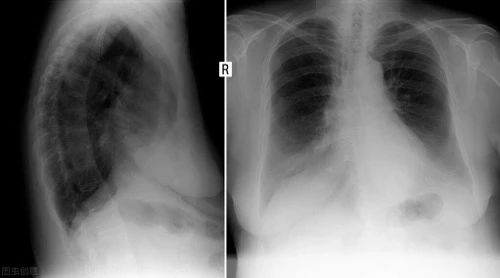

➍ 在发病 6 个月后,住院时病情更重的患者更可能呈现肺功能下降和胸部影像学异常。

这项研究的参与者都是金银潭医院的出院患者,病情较重者多,得出的研究结论,再次证实:

新冠病毒对人体的伤害不只肺部,可能影响到心脏、肝肾等多个器官;出院后短期内很难完全康复,一些症状可能会持续数月。